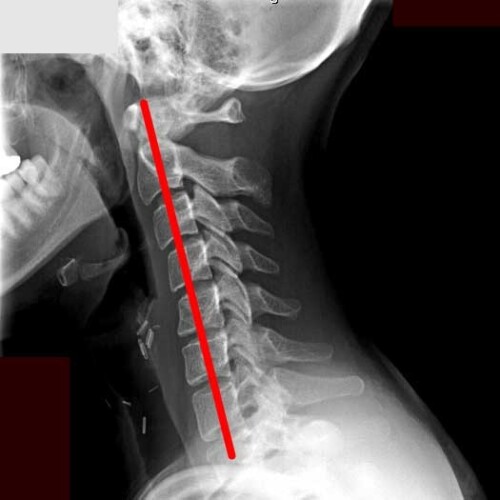

ストレートネック

普段から頭部が前方に出た姿勢を長時間取る事で頚椎の自然なカーブが無くなり、首の筋肉や椎間板にストレスがかかるようになります。

その結果肩こりが起こりやすくなり、酷くなると手の痺れや頚椎ヘルニアに移行する事があります。